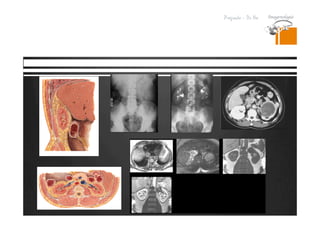

Lesiones isodensas en TC.

RESONANCIA MAGNETICA

DR. JULIO LAMA

Resonancia

Tomografia

T1

Se usa ademas para administracion de medio de contraste

Gadolinio (facilita la relajacion de los nucleos de H cercanos)